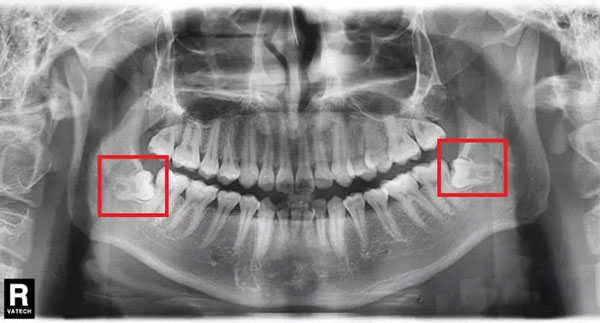

比如像下面的X片所示,双侧上颌的智齿退化缺失,而下颌双侧的智齿均前倾阻生,无法正常长出,亦无法形成咬合,实际上是没有功能的。